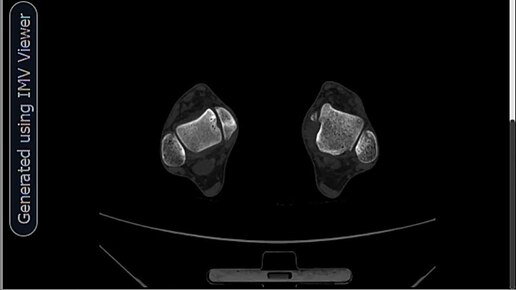

Болезнь Кенига правой таранной кости-КТ.